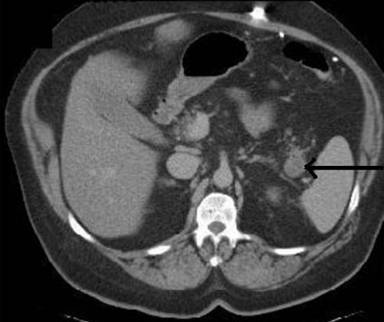

A 63-year-old white male presented with six-week history of intermittent, mild, right flank discomfort. His past medical and surgical history was unremarkable. He denied significant alcohol consumption. His physical examination apart from moderate obesity was unremarkable. A biphasic CT scan of abdomen performed for evaluation of pain revealed a 2 cm water density lesion located in the posterior pancreatic tail (Figure 1). His serum CA 19-9 and serum amylase levels were normal. He was referred to us for further evaluation of incidentally found pancreatic cystic lesion. He underwent endoscopic ultrasound (EUS) which revealed three cysts ranging in size from 4 mm to 10 mm in pancreas body (which were not identified on CT) and a multi-loculated cystic lesion measuring 2.1x1.4 cm (lesion #1)located in the pancreas tail (corroborating the CT findings). The main pancreatic duct caliber was normal. The sonographic features were suggestive of multi-side branch-IPMN (Figure 2, arrowhead). Immediately inferior to the largest multi-side branch-IPMN lesion and adjacent to the left kidney, a well-circumscribed, more solid-appearing lesion with anechoic (microcysts) intervening spaces was seen (lesion #2) (Figure 2, arrow). This lesion was not identified on his CT scan.

Figure 1. Axial CT image showing a mixed attenuation, well circumscribed lesion at the tip of pancreatic tail. |